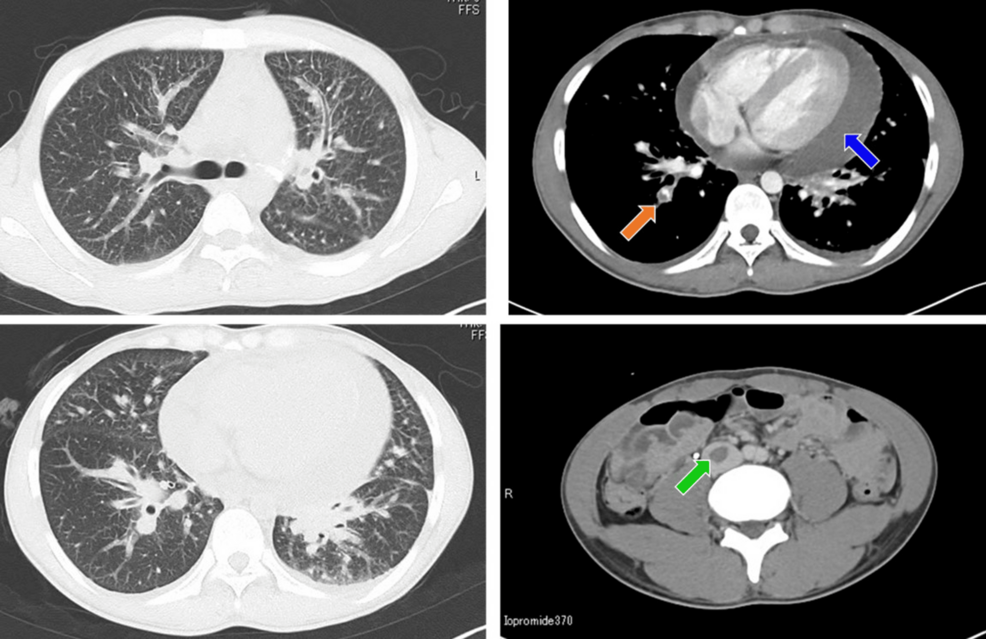

From www.cureus.com

YoungOnset, ROS1Rearranged Adenocarcinoma of the Lung With Cardiac Tamponade A Case Report What Is Plastic Lung Instead of draining out, it leaks into the airways and. Plastic bronchitis is an extremely rare respiratory disease in which patients suffer from dyspnea, chronic cough, congested lungs,. Plastic bronchitis happens when fluid collects in the lungs. This review presents current understanding of the. Plastic bronchitis happens when fluid collects in the lungs. Plastic bronchitis in adulthood should not be. What Is Plastic Lung.